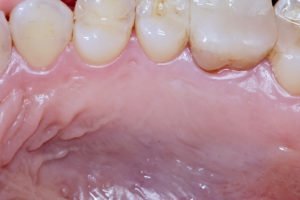

Falhas nas suturas podem levar a uma cicatrização por segunda intenção devido à necrose do retalho palatino, possível exposição óssea e, consequentemente, maior dor e morbidade pós-operatória do paciente (Figura 1). Outro aspecto importante a ser considerado em relação à área doadora está relacionado a repetidas remoções de enxertos na mesmo sítio doador. A cicatrização incorreta do palato pode acarretar em uma menor espessura de tecido conjuntivo doador e uma qualidade inferior de colágeno.

Figura 1 – Pós-operatório de sete dias da área cirúrgica doadora do enxerto de tecido conjuntivo, demonstrando uma cicatrização por segunda intenção. Observar exposição óssea devido à necrose do retalho de cobertura. O fechamento incorreto do sítio doador pode gerar maior tempo no período de cicatrização, dor e desconforto por parte do paciente. A remoção do enxerto foi realizada pela técnica de incisão única e o retalho palatino foi suturado com fio de Nylon 5-0 e suturas simples.